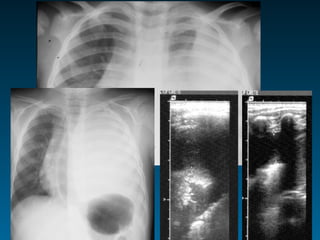

Στρογγύλη πνευμονία